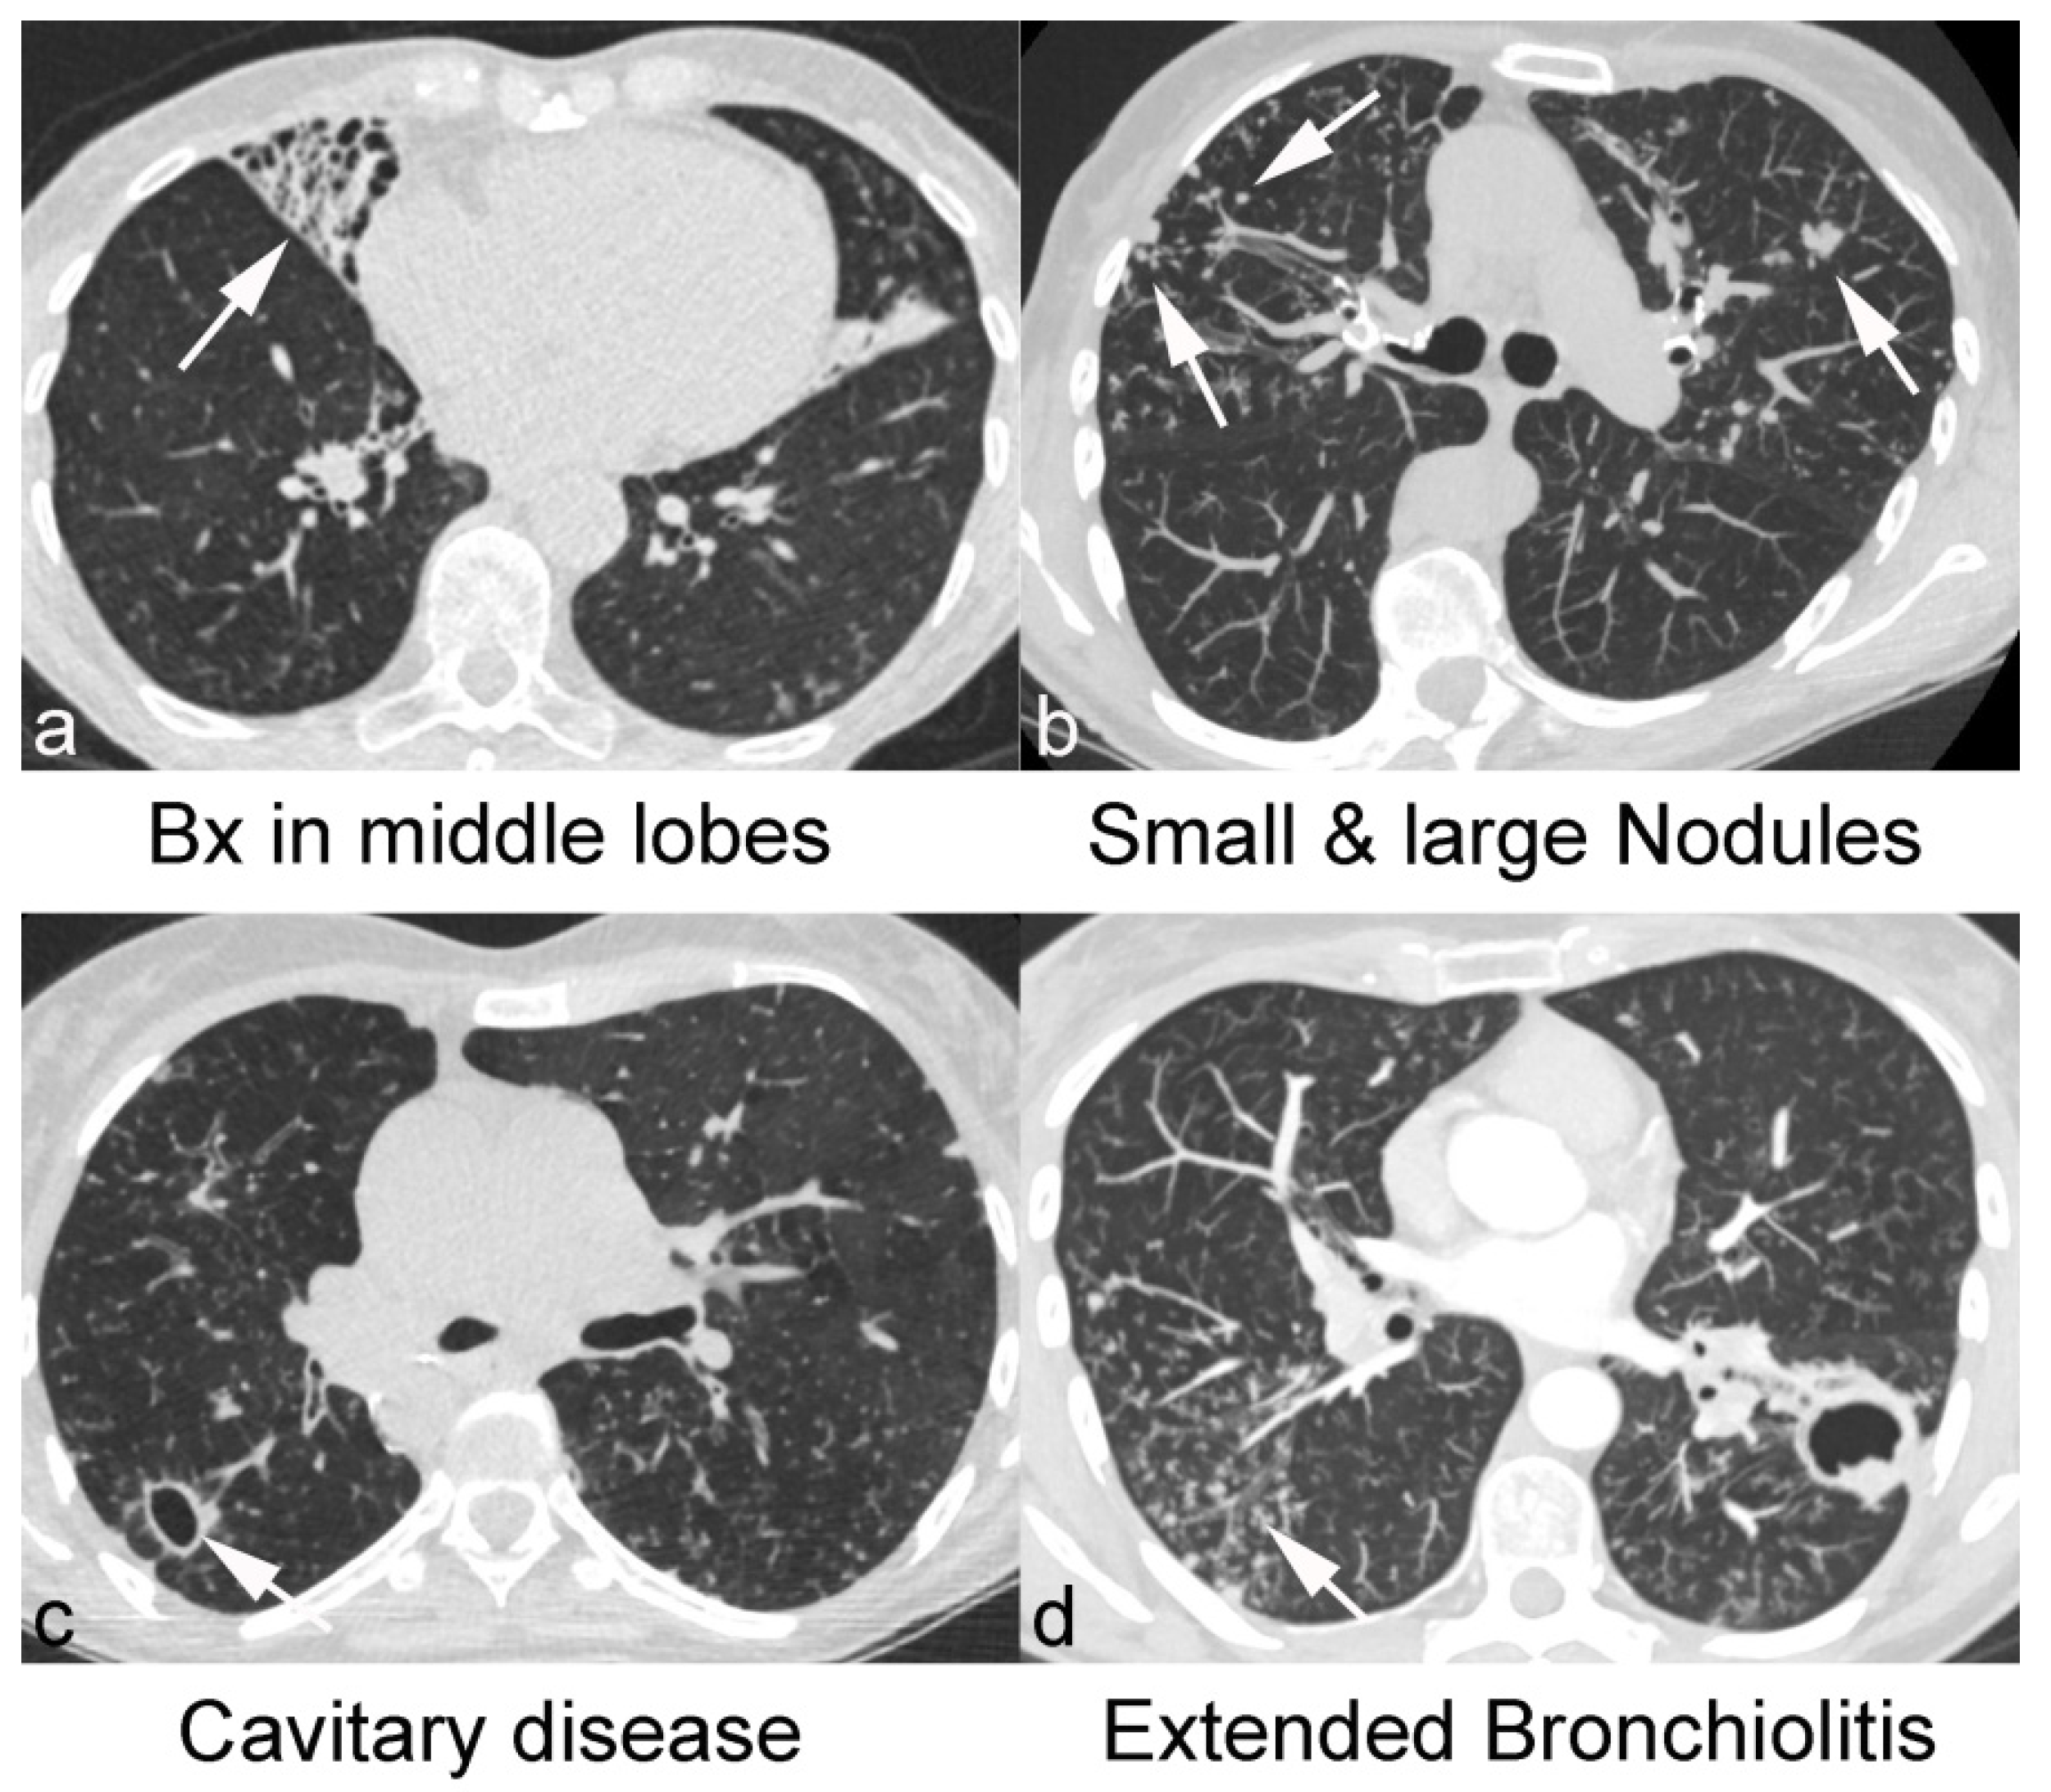

Computed Tomography in Adults with Bronchiectasis and Nontuberculous Mycobacterial Pulmonary Disease: Typical Imaging Findings

3.2. CT Features of NTM-PD and Non-NTM Bronchiectasis